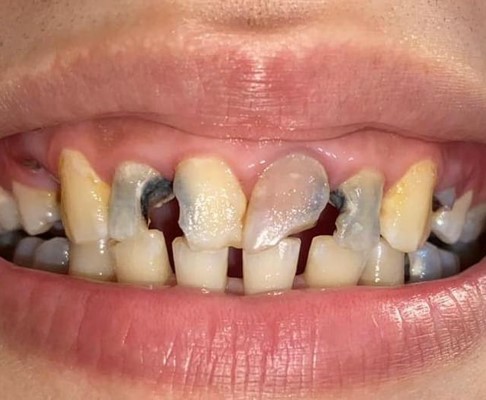

Full E-MAX 4 crowns restoration